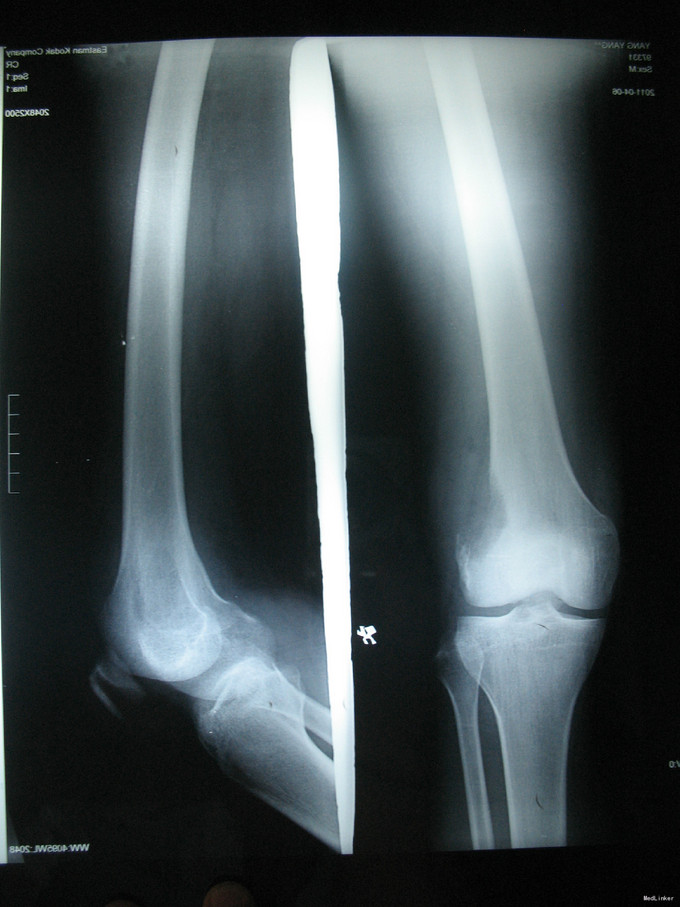

右膝上疼痛2个月肿胀一周 患者2个月前无明显诱因出现右膝上疼痛,逐渐加重,一周前活动后加重明显并开始出现肿胀,右膝关节活动受限,于当地医院行CT及MRI检查考虑为恶性肿瘤,遂来我院治疗。

右膝上股外侧肿胀明显,压痛(++),皮温略高,皮色正常,右膝关节屈伸活动明显受限。